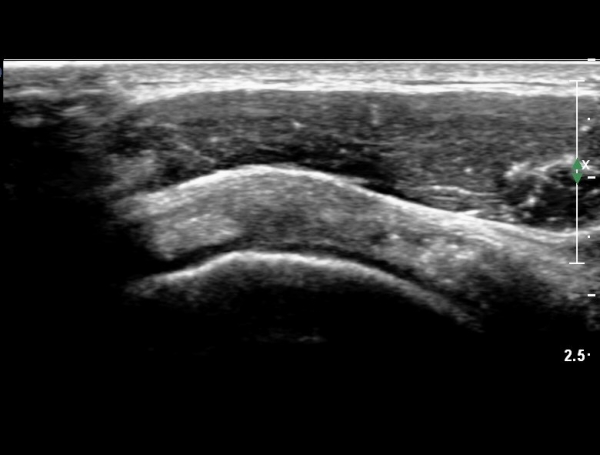

°ß°©ÇÏ±Ù°Ç Á¾´Ü¸ç°Ë»ç¿¡¼­ °Ç »óºÎ¿¡ ÀÌÁúÀûÀÎ ¿¡ÄÚ¸¦ º¸¿© °ß°©ÇÏ±Ù°Ç »óºÎ ºÎºÐÆÄ¿­ÀÌ ÃßÁ¤µÈ´Ù(»çÁø 3),

°ß°©ÇÏ±Ù°Ç ÇϺο¡¼­´Â ÀÌ»ó ¼Ò°ßÀÌ °üÂûµÇÁö ¾Ê´Â´Ù(»çÁø 4).